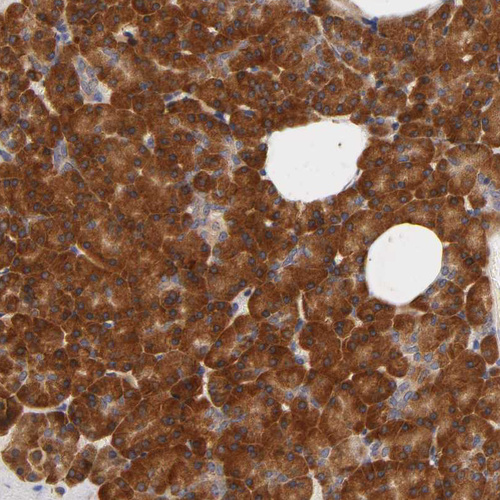

Immunohistochemical staining of human pancreas shows strong cytoplasmic positivity in exocrine glandular cells.